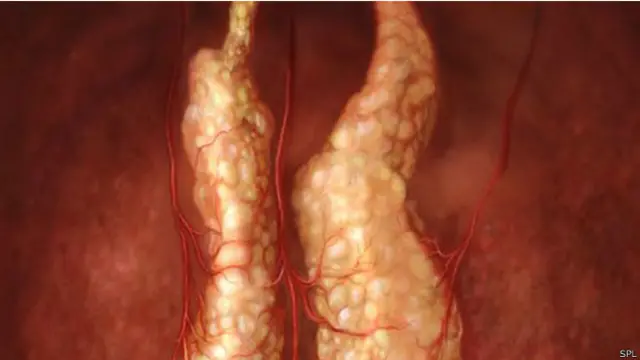

ஆங்கிலத்தில் தைமஸ் என்று அழைக்கப்படும் கழுத்துக்கணையம் என்பது உடலின் முக்கிய உறுப்பு. மனிதர்களுக்கு இது இதயத்துக்கு மேலே கழுத்துப்பகுதிக்கு கீழே அமைந்திருக்கும். இரண்டு பிரிவாக இருக்கும் இந்த கழுத்துக்கணையம் மனிதர்களின் ஆரோக்கியத்துக்கு மிகவும் அவசியமானது. காரணம் இந்த கழுத்துக்கணையத்தில் தான் மனிதர்களின் நோய் எதிர்ப்புத்தன்மைக்கு மிக மிக அவசியமான டி செல்கள் முதிர்ச்சியடைந்து ஒட்டுமொத்த உடலுக்கும் பரவுகின்றன. இந்த டி செல்கள் தான் மனித உடலின் நோய் எதிர்ப்பு சக்திக்கான அடிப்படை கவசமாக செயற்பட்டு, மனித உடலுக்குள் புகமுயலும் எல்லாவிதமான நோய்க்கிருமிகளையும் தடுத்து தாக்கி அழிக்கின்றன.